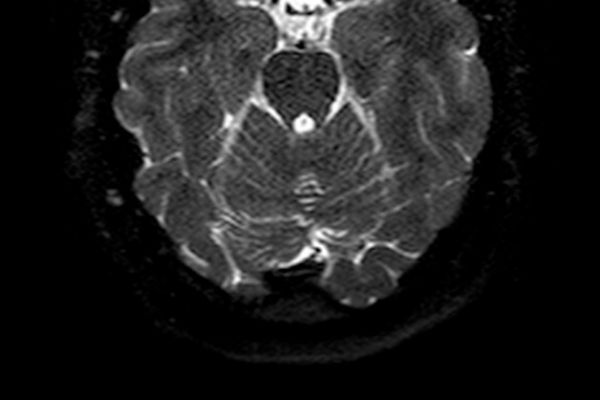

Die Magnetresonanztomographie nutzt keine Röntgenstrahlen sondern Magnetfelder und hochfrequente elektromagnetische Wellen. Das durch hochempfindliche Antennen gewonnene Signal wird in einem komplizierten Auslese- und Messverfahren umgesetzt und in ein Bild umgewandelt.

Der Vorteil der MRT ist die oft bessere Darstellbarkeit entzündlicher und tumoröser Veränderungen in sämtlichen Weichteil-Geweben, bzw. -Strukturen; Nerven- und Hirngewebe werden z.T. erst durch die MRT-Untersuchung hinreichend beurteilbar. Oft wird Kontrastmittel zusätzlich benötigt, um Entzündungsherde oder auch Tumorgewebe noch besser darzustellen.

• Gehirn und Nervenstrukturen